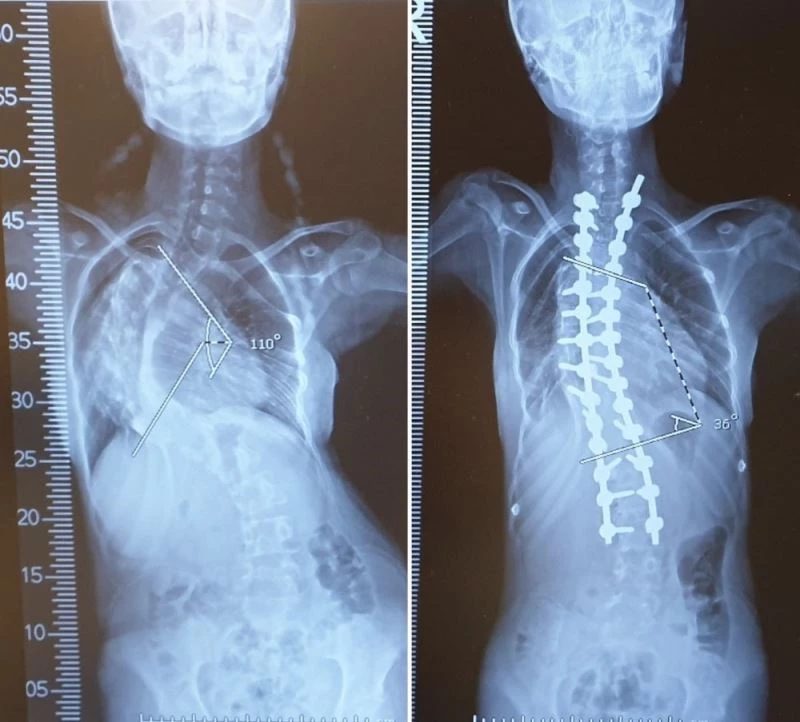

MERSİN (İHA) – Mersin’de yaşayan ve omurgasında 110 derecelik eğrilik bulunan 13 yaşındaki Medine Şengül, VM Medical Park Mersin Hastanesinde 5 saat süren başarılı operasyonla sağlığına kavuştu.

Omurgasındaki 110 derecelik eğrilik nedeniyle yürümekte zorlanan ve hayatında büyük güçlükler çeken Medine Şengül, tedavi için VM Medical Park Mersin Hastanesine başvurdu. Yapılan kontroller sonucunda skolyoz ameliyatı olması kararı alınan hasta, Ortopedi ve Travmatoloji Uzmanı Prof. Dr. Mustafa Çeliktaş ve ekibinin katıldığı 5 saat süren operasyon sonucunda omurgasındaki eğrilik giderilerek sağlığına kavuştu.

Başarılı bir şekilde sonuçlanan ameliyatın ardından açıklama yapan Prof. Dr. Mustafa Çeliktaş da “Hastamız Medine bize başvurduktan sonra yaptığımız tetkiklerde normalde düz olması gereken omurgasının yaklaşık 110 derece kadar eğrildiğini gördük. Hastalık oldukça ilerlemiş durumdaydı. Skolyoz hastalığını erken dönemde yakaladığımızda tamamen düzeltmek mümkün. Fakat ileri derece eğriliklerde amacımız hastanın zarar görmesini engelleyerek kabul edilebilir seviyelere düşürmek. Medine hastamızda da bu eğrilik ameliyattan sonra büyük oranda düzeldi. Yaptığımız kontrolde omurgasındaki eğriliğin dışarıdan hiç fark edilmeyecek seviyeye geldiğini gördük. Skolyozda önemli olan hastalığın tanısının erken teşhis edilmesi ve erken tedavi edilmesi. Fakat geç yakalansa dahi yapılacak özellikli ameliyatlarla deformitenin önüne geçilebilmektedir” diye konuştu.